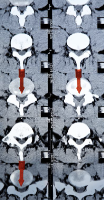

디스크 탈출증은 디스크의 중심부인 수핵 섬유륜이 외부로 튀어나오는 상태를 말합니다. 이때 수핵 섬유륜이 주변의 신경을 압박하면 허리통증과 함께 다리에 통증이나 저림, 마비 등의 증상이 나타날 수 있습니다. 이러한 증상을 방사통이라고 합니다. 디스크 탈출증의 치료방법은 보존적 치료와 시술적 치료, 수술적 치료로 나눌 수 있습니다. 보존적 치료는 디스크 변성증과 비슷하게 휴식, 약물, 물리치료, 주사치료 등을 시도합니다. 시술적 치료는 바늘 구멍이나 작은 피부 절개로 병변에 직접 접근하여 치료하는 방법입니다. 예를 들어 신경 차단술은 병변에 약물을 주입하여 통증을 감소시키고 신경 주변의 연부조직 부종을 감소시키는 방법입니다. 고주파 수핵 감압술이나 레이저 치료는 병변에 열을 가하여 탈출된 디스크나 통증을 유발하는 디스크 내 병소를 소작-응축 시켜주는 방법입니다. 내시경하 추간판 제거술은 옆구리 쪽에서 척추에 정상적으로 존재하는 신경구멍을 통해 내시경을 삽입하여 탈출된 디스크를 제거하는 방법입니다. 수술적 치료는 병변 부위를 넓게 절개하여 탈출된 디스크를 제거하고, 필요한 경우에는 척추뼈를 고정하는 방법입니다.